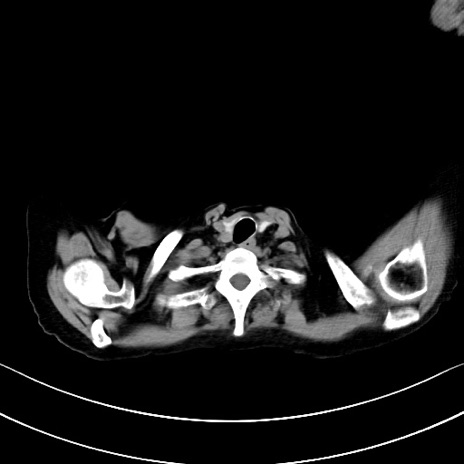

横断像

他院CT